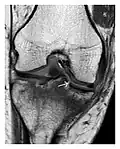

Figure 1: A 56-year-old woman presenting with left knee pain after a fall. (a) Initial anteroposterior radiograph was considered normal, however, subtle cortical disruption of the anterior rim of the medial tibial plateau, medial to the tibial spine, is noted (arrow). (b) Coronal T1-weighted MRI confirms the cortical disruption (arrow) and shows extensive fracture through the proximal tibia. (c) Coronal proton density-weighted image with fat saturation shows extensive edema in the subchondral bone. Note also hypersignal adjacent to the medial collateral ligament corresponding to a grade I sprain (arrowheads).[1]